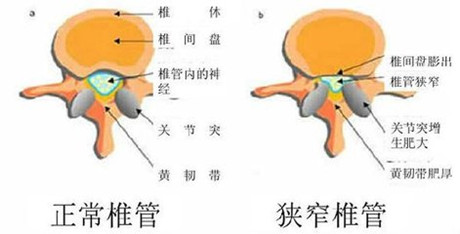

诱发腰椎管狭窄原因是什么?

诱发腰椎管狭窄的原因:

2、退变性腰椎管狭窄:人们的脊柱,随着年龄的增长,会逐渐出现老化,并发生退行性病变,从而引发各种骨科疾病的出现。退变性腰椎管狭窄就是由脊柱发生退行性病变所引起的。

3、脊柱滑脱性腰椎管狭窄:腰椎上、下关节突之间的狭窄部分骨质结构相对薄弱,容易发生腰椎峡部崩裂。腰椎峡部崩裂、不连或是退变,都会引发脊椎滑脱,这样会引发脊柱滑脱性腰椎管狭窄。当发生脊椎滑脱时,会使椎管进一步变窄,同时脊椎滑脱,可促进退行性变,更加重椎管狭窄。》》》腰椎椎管狭窄对身体的危害有哪些?点击咨询